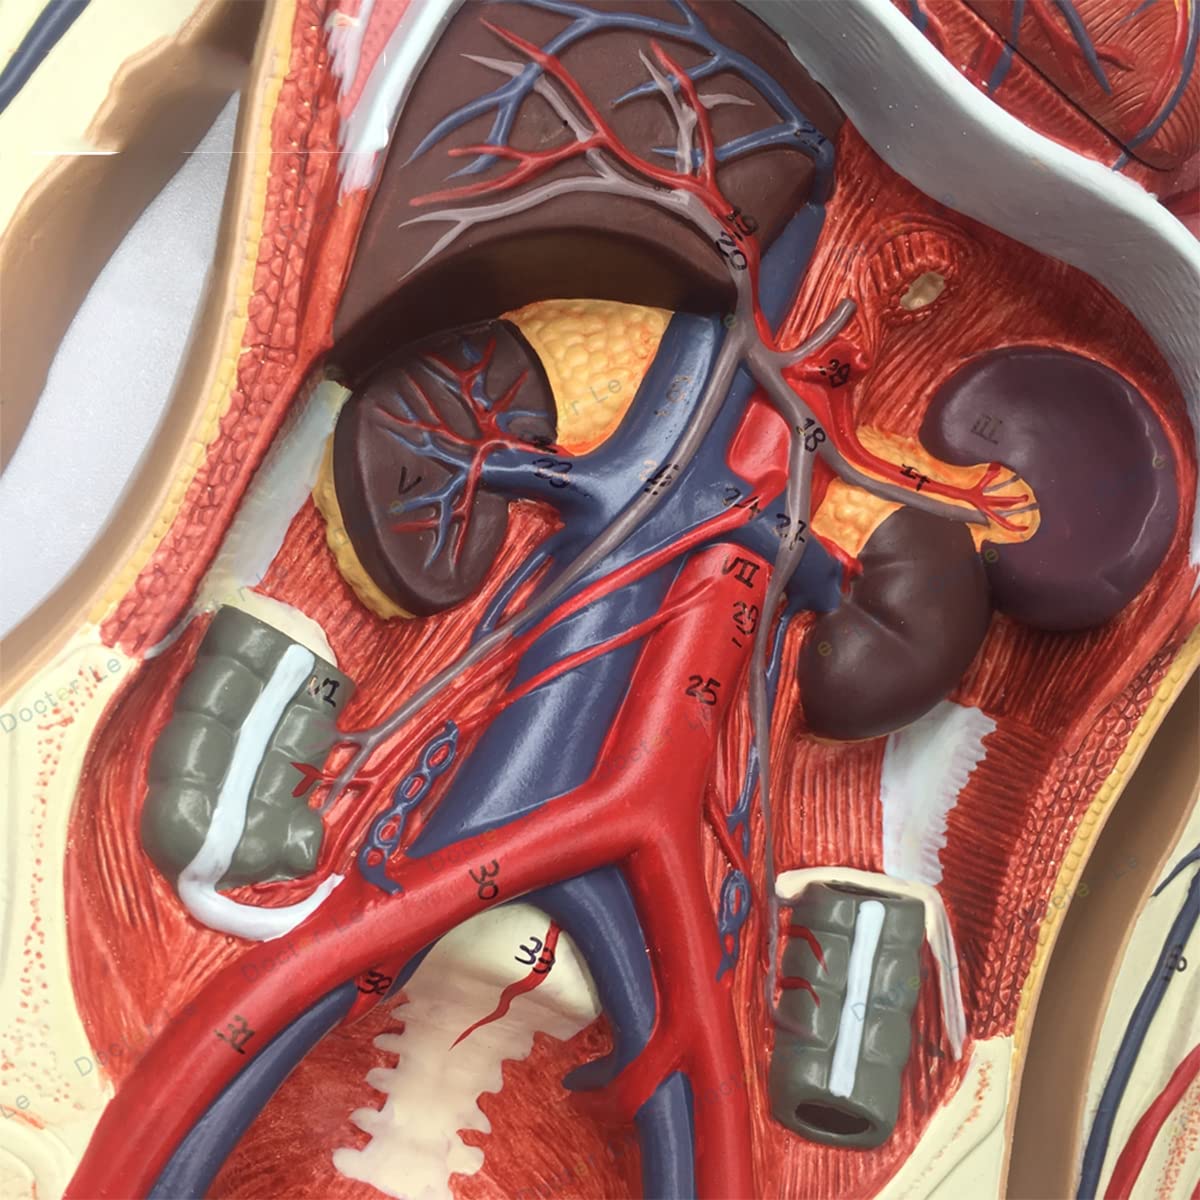

- Features: This model shows the structure of blood circulation in various parts of the human body. The circulatory system is the channel through which blood flows in the body and is divided into two parts: the cardiovascular system and the lymphatic system. Blood circulation route: superior and inferior vena cava → right atrium → right ventricle → pulmonary artery - → alveolar surrounding → pulmonary veins - >> left atrium → left ventricle → aorta - → systemic tissues (except lung). Product Size: Using this model helps to understand the composition and structure of human blood circulation. The size of the model is 1/2 the size of the human blood circulatory system. Product size: 90*30 cm/35.4*11.8 inches. High Quality: High-quality prototypes, sturdy hand-made, not fragile, made of high-quality environmentally friendly PVC, fine workmanship, creating good objects with clear shapes and rich details. Meticulous workmanship: The model has meticulous workmanship, realistic details, clear texture, easy to use and easy to observe. This product comes with a base, which is convenient for learning and teaching. Good Teaching Aids: This collection is designed for anatomy professionals and students. We are sure you will love these models. Can also be given as a gift to educators or doctors, excellent educational tool for students/teachers/professionals.